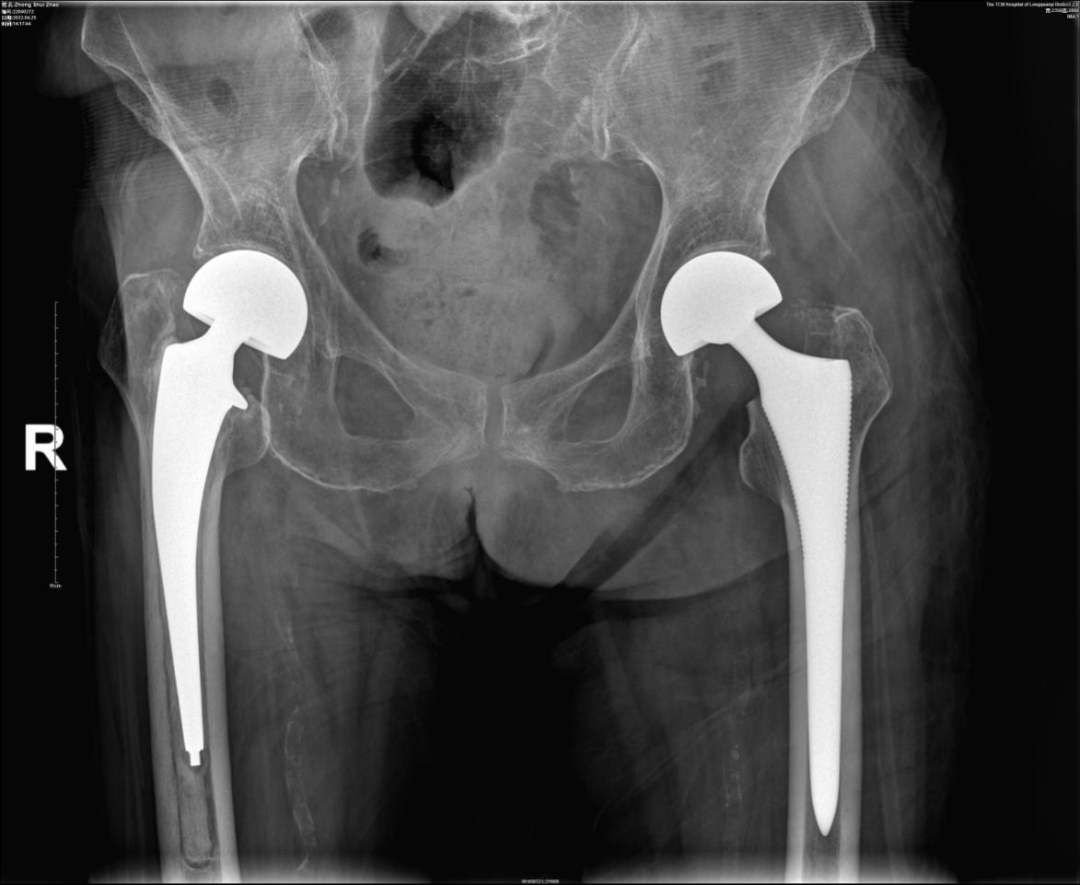

经过充分的术前准备后,于2022年4月20日在气管插管静脉全身麻醉下,徐驰主任及其团队为钟奶奶实施了“左侧人工半髋关节置换术”,手术非常顺利,术后第3天钟奶奶就下地开始走路了!目前钟奶奶已经回到家中休养一个多月了,我们电话联系了钟奶奶的家人,得知钟奶奶目前恢复很好,钟奶奶的家人对我们医院和骨科团队表示非常感谢!后期我们也会对钟奶奶的恢复情况进行定期随访和关注。

术后X片